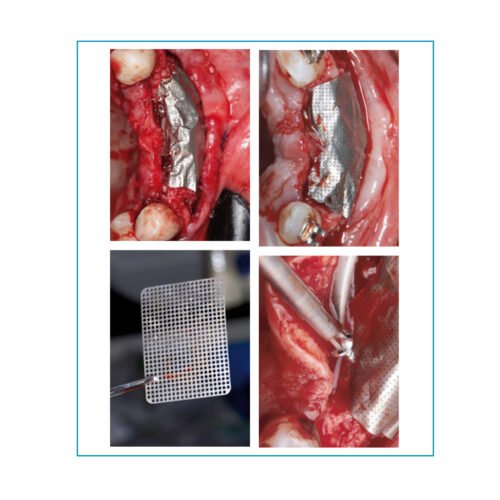

Surgitime Titanio 0,15mm

Surgitime Titanio 0,85mm

Surgitime Titanio 0,85mm Bold

Surgitime Titanio Seal